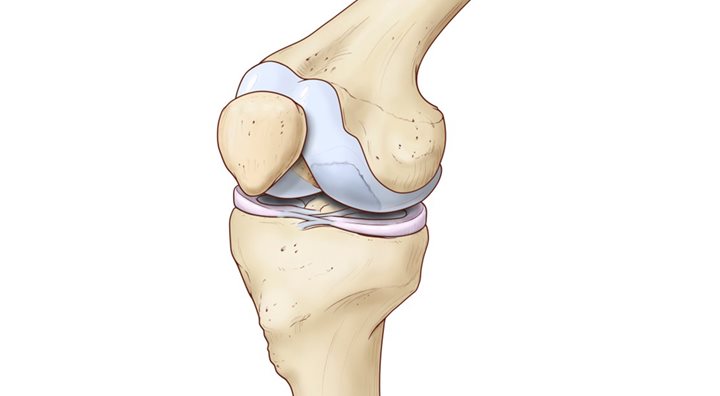

Рисунки Суставов: Анатомические Иллюстрации